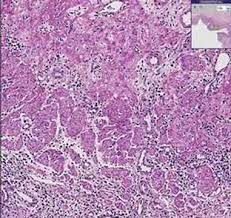

The diagnosis of herpes simplex virus (hsv) esophagitis is made at endoscopy. The acute inflammation can be caused by infections, ingestion of irritative chemicals, drugs such as nsaids, chemotherapy, and radiation. The diagnosis of hsv and cmv esophagitis, and to develop a predictive model for differentiating cmv esophagitis from hsv esophagitis. Esophagitis caused by herpes simplex virus (hsv) is frequently documented during periods of immunosuppression in patients infected with human immunodeficiency virus (hiv). Concomitant herpetic and candidal esophagitis is a very rare disease that had not been reported in uremic patients.

Esophagitis caused by herpes simplex virus (hsv) is frequently documented during periods of immunosuppression in patients infected with human immunodeficiency virus (hiv). Lymphocytic esophagitis is characterized by high numbers of intraepithelial lymphocytes (iels) gathered mainly around peripapillary fields and by none (n = 12) to occasional (n = 8) cd15+ intraepithelial granulocytes. The histology of herpes infections is very distinctive. The acute inflammation can be caused by infections, ingestion of irritative chemicals, drugs such as nsaids, chemotherapy, and radiation. His immunological work up showed normal level of immunoglobulins and his white blood cells subpopulations were normal. We reviewed 16 cases of hsv esophagitis diagnosed from january 1982 to march 2016. The low power pattern of a typical lesion. Hsv esophagitis is usually identified in patients with aids or other significant immunosuppressive conditions, although cases in healthy adults also occur.

The differential diagnosis in a patient with a swallowing disorder or other problem with food intake includes both local and systemic problems. Lymphocytic esophagitis is characterized by high numbers of intraepithelial lymphocytes (iels) gathered mainly around peripapillary fields and by none (n = 12) to occasional (n = 8) cd15+ intraepithelial granulocytes. Webpathology is a free educational resource with 11065 high quality pathology images of benign and malignant neoplasms and related entities. The diagnosis of hsv and cmv esophagitis, and to develop a predictive model for differentiating cmv esophagitis from hsv esophagitis. A novel histologic phenotype of chronic esophagitis, ie, lymphocytic esophagitis, is reported in 20 patients.